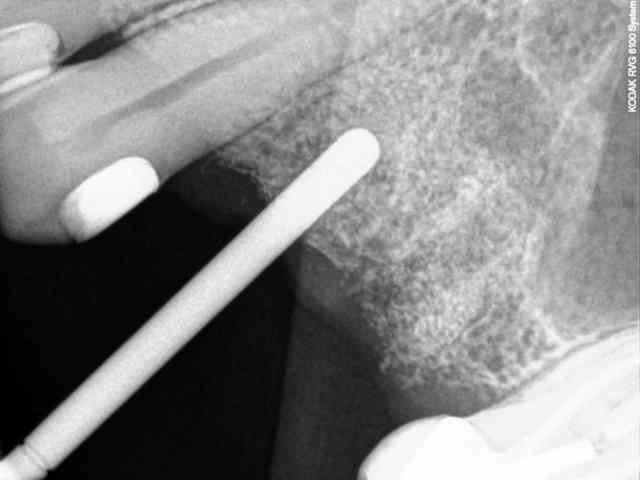

7-8-9-10-11- les radios